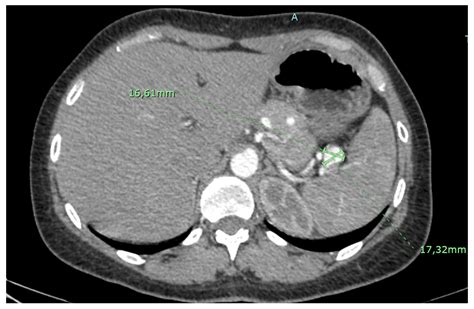

Computed Tomography (CT) Scan: Provides detailed cross-sectional images of the abdomen. It is often used to confirm the presence of an aneurysm and assess its size and location.